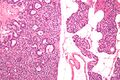

صورة مجهرية لغدوم الجار درقية (يسار) وغدة جارات درقية طبيعية (يمين). صبغة الهيماتوكسيلين واليوزين.

الصور المجهرية